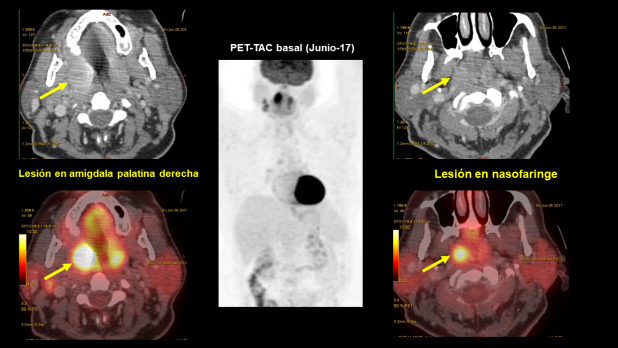

Un estudio PET-CT con FDG muestra (figs. 1 y 2):

Lesión en nasofaringe con incremento de actividad metabólica (SUV 7,4), con una lesión seudonodular en la porción central, de 16 x 11 mm.

Lesión en amígdala palatina derecha, de aproximadamente 23 x 24 mm. Ambas amígdalas presentan un aumento de captación de FDG, a predominio derecho (SUV 15-17).